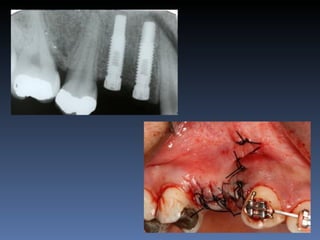

BOX 4

Ville Victorazzo Carmo

Idade – 20 anos

Sexo – Masculino

Raça – Caucasiana

ASA – I

Data- 27-04-2012

Diagnóstico: Desdentado da zona 2.1,

pré-regenerada.

Plano de tratamento: Instalação de implante endo-

ósseos ( 2.1 ) para reabilitação protética fixa.